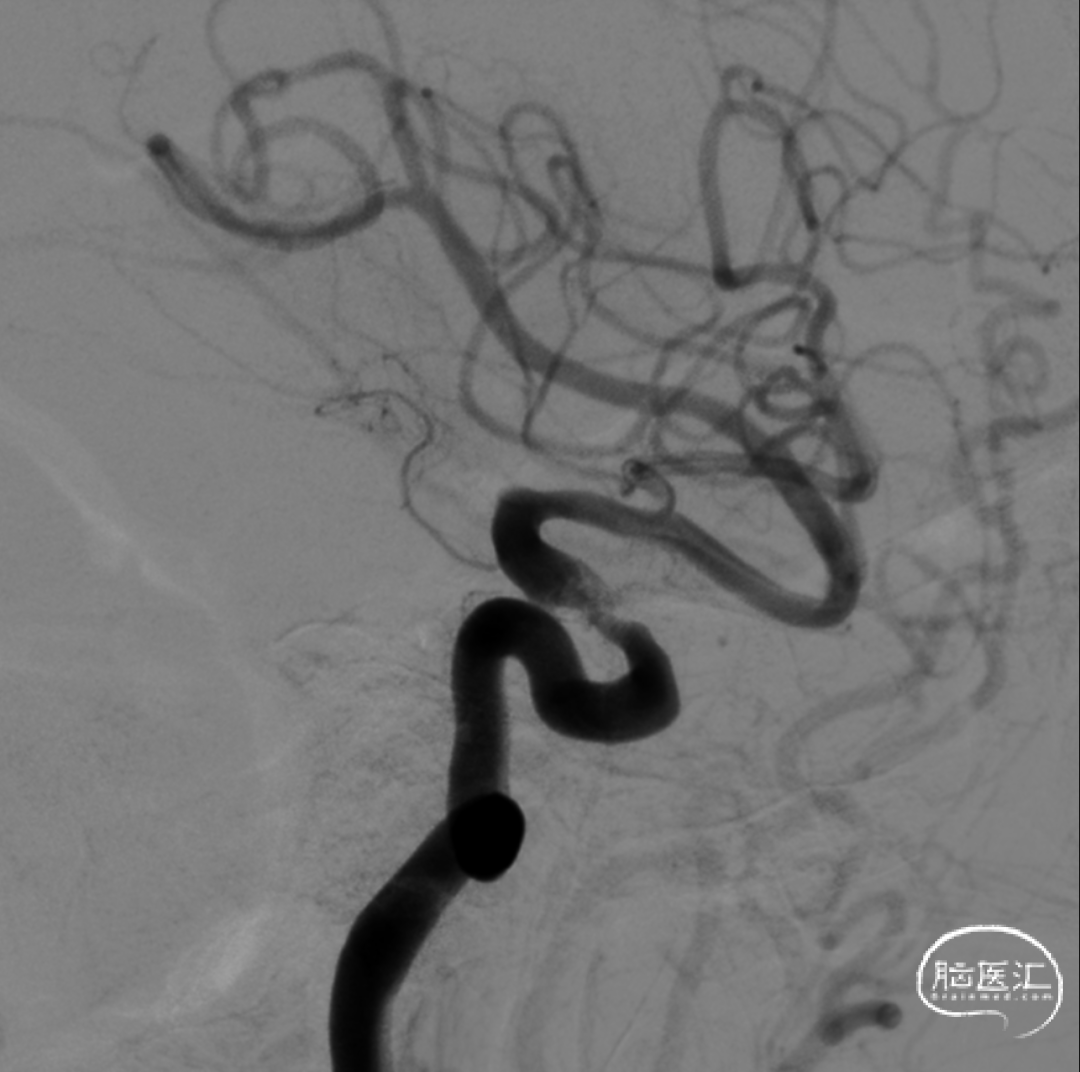

多角度造影明确左侧颈内动脉眼动脉段重度狭窄。

正位造影

在Synchro14微导丝引导下将Gateway3.5-9mm球囊送至狭窄段,缓慢扩张球囊至6atm,撤除球囊压力后造影见狭窄改善。

造影见狭窄明显改善